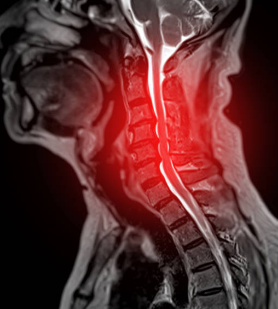

๋ชฉ๋์คํฌ๋ ๊ฒฝ์ถ ์ถ๊ฐํ ํ์ถ ์ฆ์ด๋ผ๊ณ ๋ ๋ถ๋ฆฌ๊ณ ์์ต๋๋ค. ๊ฒฝ์ถ ์ฌ์ด์ ์ถ๊ฐํ์ด ๋ค์ชฝ์ผ๋ก ๋์ถ๋์ด ์ ๊ฒฝ๊ทผ์ด๋ ์ฒ์๋ฅผ ์๋ฐํ๋ ์งํ์ผ๋ก ๋ถ๋ฆฝ๋๋ค. ์ฐ๋ฆฌ์ ์ฒ์ถ๋ 24๊ฐ์ ์ฒ์ฃผ๋ผ๋ก ์ด๋ฃจ์ด์ ธ ์์ผ๋ฉฐ, ๊ฐ ์ฒ์ฃผ๋ผ ์ฌ์ด์๋ ์ถ๊ฐํ์ด๋ผ๋ ์ฐ๊ณจํ์ด ์์ต๋๋ค. ์ถ๊ฐํ์ ์ฒ์ฃผ๋ผ ์ฌ์ด์ ์ฟ ์  ์ญํ ์ ํ์ฌ ์ถฉ๊ฒฉ์ ํก์ํ๊ณ ์ฒ์ฃผ๋ผ์ ์์ง์์ ์ํํ๊ฒ ํฉ๋๋ค. ํ์ง๋ง, ๋ ธํ ์ธ์, ์์ธ ๋ถ๋ ๋ฑ์ผ๋ก ์ธํด ์ถ๊ฐํ์ด ์์๋๊ฑฐ๋ ์ฝํด์ง๋ฉด, ๋ด๋ถ์ ์ํต์ด ๋ค์ชฝ์ผ๋ก ๋์ถ๋์ด ์ ๊ฒฝ์ ์๋ฐํ ์ ์์ต๋๋ค. ์ด๊ฒ์ด ๋ฐ๋ก ๋ชฉ๋์คํฌ์ ๋๋ค.